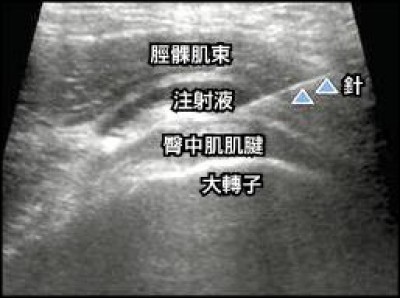

喜愛慢跑的民眾要注意腿部健康。台大醫院北護分院收治一名病患,因病患平常有慢跑習慣,但

大腿外側常疼痛且彎曲伸直時有「喀拉」異常聲響

,經超音波診療後確認是「彈響髖」(俗稱喀拉腿)。